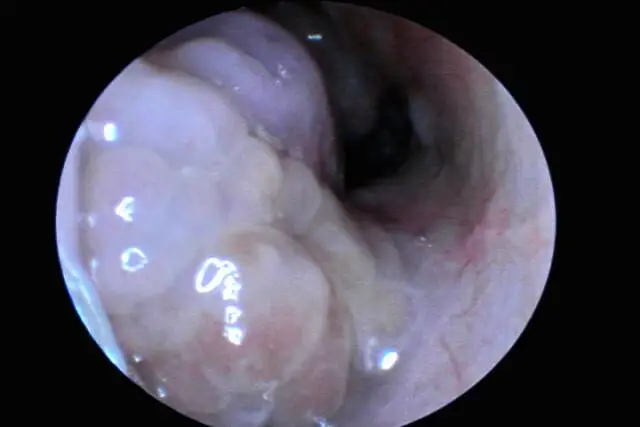

南京耳鼻喉科医院_老年人鼻息肉治疗指南

鼻息肉虽非重大疾病,却会引发鼻腔分泌物增多、鼻塞等症状,严重影响老年人的日常生活与作息。临床中,药物治疗和手术治疗均能有效应对鼻息肉,结合老年人的身体特点,选择合适的治疗方案尤为关键。